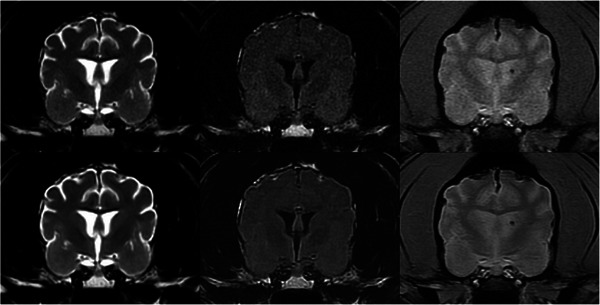

In this analytical cross-sectional method comparison study, we evaluated brain MR images in 30 dogs and cats with and without using a DICOM-based deep-learning (DL) denoising algorithm developed specifically for veterinary patients. Quantitative comparison was performed by measuring signal-to-noise (SNR) and contrast-to-noise ratios (CNR) on the same T2-weighted (T2W), T2-FLAIR, and Gradient Echo (GRE) MR brain images in each patient (native images and after denoising) in identical regions of interest. Qualitative comparisons were then conducted: three experienced veterinary radiologists independently evaluated each patient's T2W, T2-FLAIR, and GRE image series. Native and denoised images were evaluated separately, with observers blinded to the type of images they were assessing. For each image type (native and denoised) and pulse sequence type image, they assigned a subjective grade of coarseness, contrast, and overall quality. For all image series tested (T2W, T2-FLAIR, and GRE), the SNRs of cortical gray matter, subcortical white matter, deep gray matter, and internal capsule were statistically significantly higher on images treated with DL denoising algorithm than native images. Similarly, for all image series types tested, the CNRs between cortical gray and white matter and between deep gray matter and internal capsule were significantly higher on DL algorithm-treated images than native images. The qualitative analysis confirmed these results, with generally better coarseness, contrast, and overall quality scores for the images treated with the DL denoising algorithm. In this study, this DICOM-based DL denoising algorithm reduced noise in 1.5T MRI canine and feline brain images, and radiologists' perceived image quality improved.

Abstract Image